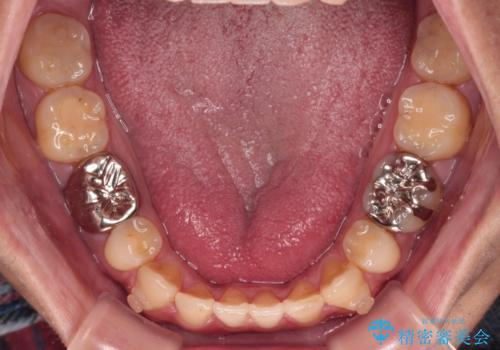

- 抜歯矯正の後戻りを気にして来院された患者様です。

舌の突出癖によるオープンバイトになり、前歯の叢生が後戻りしていました。

舌のトレーニングを行いながら、インビザラインを用いて矯正治療を行うこととしました。

インビザラインの特性を活用して奥歯の咬み合わせを圧下させることで、前歯のオープンバイトを改善さえることができました。